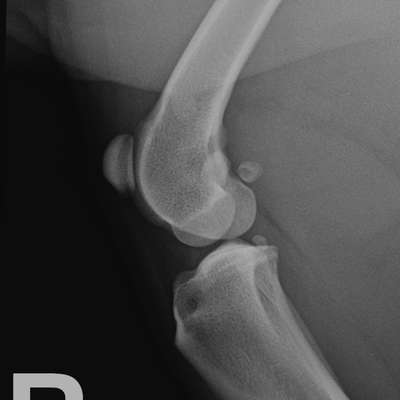

Ich hab’s ich mal das eine Röntgenbild angehangen für das rechte Knie.

Maja sollte nämlich auch nüchtern zum Termin kommen, um ein Röntgenbild in Narkose zu machen und das ist zum Beispiel auch nicht passiert. Also es wurde direkt gesagt sozusagen operieren, obwohl sie sich nicht 100-prozentig sicher ist, dass da was kaputt ist. Sie hat versucht den Schubladentest zu machen aber bei einer sehr muskulär Bulldogge ist das so gut wie unmöglich und sie meinte da etwas Instabilität zu spüren.

Bin gespannt was eure Meinung ist